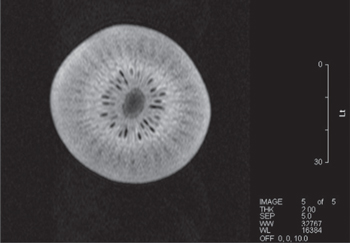

With the magnet operating stably, and with a good level of shim achieved, we performed some MRI images on fruit. We were able to achieve both spin-echo [19] as can be seen in figures 22 and 23 and gradient-echo [19] images as can be seen in figures 24 and 25.

Standard image High-resolution imageFigure 23. Spin-echo image of kiwi fruit. Axial image, 80 × 80 mm FOV. TR = 3000 ms, TE = 75 ms. 2 mm slice.

Download figure:

Standard image High-resolution imageIn previous work, we have only been able to successfully demonstrate the formation of spin-echo images. Refocusing of spins using a 180° radio-frequency pulse as performed in spin-echo imaging is less sensitive to eddy current effects than using a gradient pulse to achieve the same effect. Achievement of gradient echo images without having to use pre-emphasis techniques to accommodate eddy current effects is indicative that interaction between the magnet and gradient set is minimal. This is in part due to the use of a shielded gradient coil, but also due to the optimisation of the cooling manifold to minimise eddy current formation.